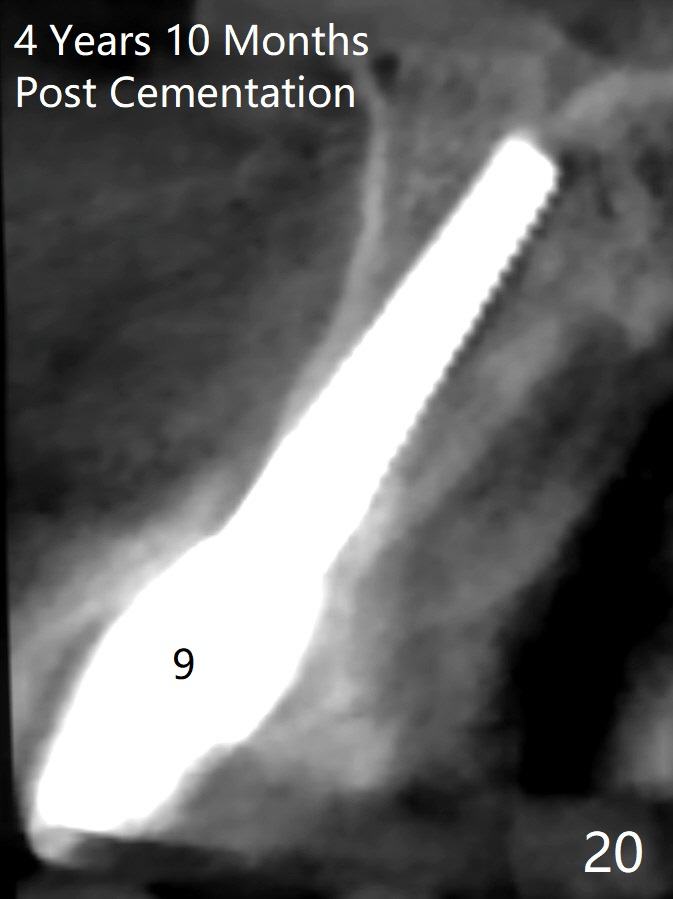

These two anterior implants remain stable 2 months 20 days postop, since one of the immediate provisionals has incisal chip (Fig.11 *) while both of them are splinted (<) to increase retention. There is no complain about paresthesia around the incisal papilla due to separation of the nasopalatine nerve. Mesiodens sockets disappear 7 months postop (Fig.13). There is no bone loss 2 years 9 months postop (Fig.14 panoramus) or 4 years 10 months postop (Fig.15,16 CT). The buccal gingiva is reddish and swollen with bleed on probing and history of pain 7 years post cementation (Fig.17). There is no bone loss in PA (Fig.18). The buccal plate at #9 is thinner than that at #8 4 years 10 months post cementation (Fig.19,20).